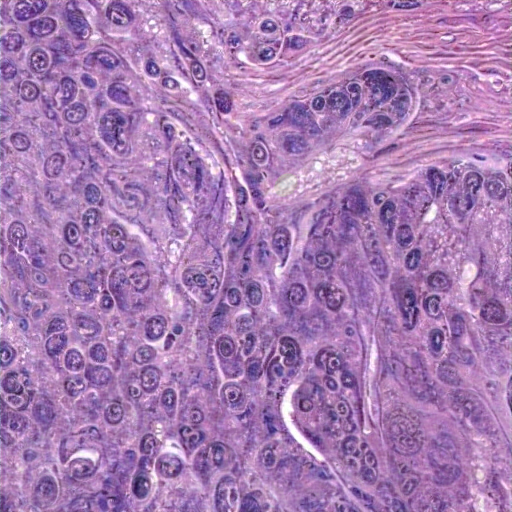

The tissue displays pleomorphism, hyperchromatic enlarged nuclei, and a high nuclear-to-cytoplasmic ratio with prominent nucleoli, indicating potential malignancy. Areas show dense cellularity, loss of normal stratification, with invasive, atypical cells and stromal invasive squamous cell carcinoma. Moderate inflammatory cells are also present. Keratin pearls confirms a poorly differentiated squamous intraepithelial lesion ( (HSIL), likely an invasive carcinoma. Active mitotic figures confirm rapid cell division a high proliferative index known as a neoplastic condition in the epithelium, along with tissue disorganization features deviates from squamous epithelium, consistent with invasive squamous cell carcinoma. Key findings include include architectural disorder and abnormal mitotic figures, and invasive, atypical cells into fibrous, inflamed stroma, with spindle-shaped cells.

The tissue image shows dense, irregular cell clusters with hyperchromatic nuclei and prominent nucleoli, suggesting pleomorphism. Scant cytoplasm and a high nuclear-to-cytoplasmic ratio indicate potential invasiveness. Differential diagnosis: endometrial carcinoma. Fibrosis, vascularization, pink stromal material, and inflammatory cells hint at hyperplasia or carcinoma. Compressed glands examined by atypical epithelial cells are noted, but definitive diagnosis requires further testing. The history of endometrial cancer, PR, endometrioid adenal adenocarcinoma, with overall disorganized architecture and pleomorphism, likely support the uterus. The features suggest a high-grade, aggressive, uncontrolled vascularization, cellular proliferation with overcrosing blue-staining stromal cells and absent normal glandular structures. This suggests a diagnosis of adenocinoma, raising concern for endometrial dyslasia postmenopausal bleeding context.

The tissue section exhibits severe pleomorphism, hyperchromatic and varied nuclei sizes with prominent nucleoli, and disorganized architecture lacking recognizable structures. Features include eosinophilic cytoplasm, dense cellular cohesion, fibrous connective tissue, and inflammatory infiltration. These findings suggest a diagnosis of a malignant addomy tum process, characterized by atypical cellular morphology, prominent nucleoli, and increased cellular activity proliferation. Possible necrotic debris supports the aggressive tumor behavior and are indicative of poorly differentiated adenocarcinoma or adenocarcinoma. These characteristics primarily display mild to moderate altered colorectal matrix or fibrosis aligning with atypical glandular morphological atypia including cell proliferation and polarity, lacking normal gastrointestinal mucosa with glandular differentiation.